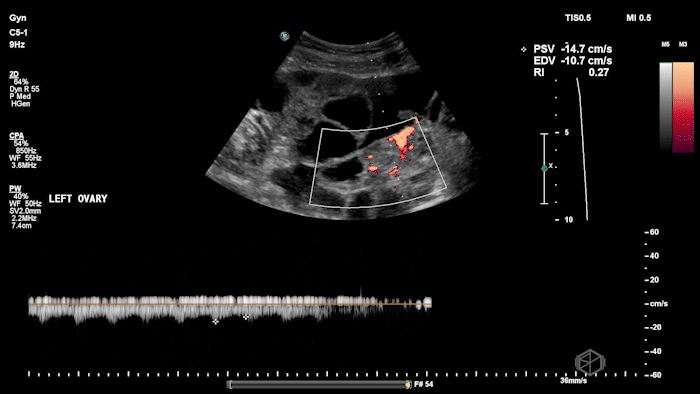

She grabbed the probe, and working with Dr. Zimmerman, saw the following:

There is moderate free fluid, no obvious pleural effusions. The bilateral ovaries are enlarged with multiple cystic structures. There are normal arterial and venous waveforms for both ovaries.

• Preserved ovarian arterial and venous flow helps distinguish OHSS from acute ovarian torsion, where flow may be compromised.